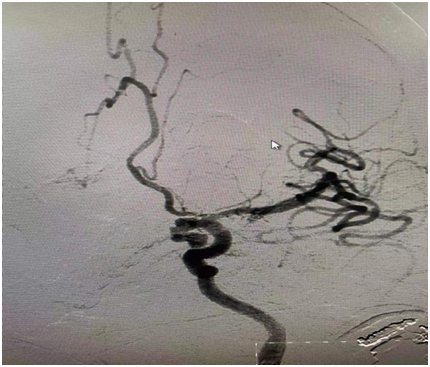

55歲的女性患者,因“頭痛伴神志不清2小時”來醫(yī)院急診科就診,入院后立即進入腦卒中綠色通道,檢查發(fā)現(xiàn)患者系腦內(nèi)“炸彈”爆炸了——后交通動脈瘤破裂出血、動脈瘤分葉,形態(tài)極像了兩個共蒂生長的“荔枝”,常規(guī)手術方法難以救治。神經(jīng)外科團隊迅速制定急救方案,在與患者家屬充分溝通后,決定采用先進的3D數(shù)字減影技術,為其實施雙導管微創(chuàng)栓塞術搶救治療。

6月1日,在導管室、麻醉科等相關科室的通力合作下,手術如期進行。由于動脈瘤共蒂生長并長期在血流沖擊下,介入導管難以分別進入兩個“荔枝”進行栓塞。神外團隊充分利用3D數(shù)字減影技術,大角度多方位旋轉(zhuǎn),兩根微導管精心塑形超選。手術室里,只有監(jiān)護儀滴答、滴答的聲音,時間一分一秒地過去了,神經(jīng)外科醫(yī)師們穿著沉重的鉛衣,汗水早已濕透了。兩根微導管在神外醫(yī)師的手中順利地分別進入了“荔枝”,并良好填塞,“炸彈”被成功拆除了,僅僅不到二小時,手術取得圓滿成功!

圖1:后交通分葉狀動脈瘤

圖3 動脈瘤栓塞滿意